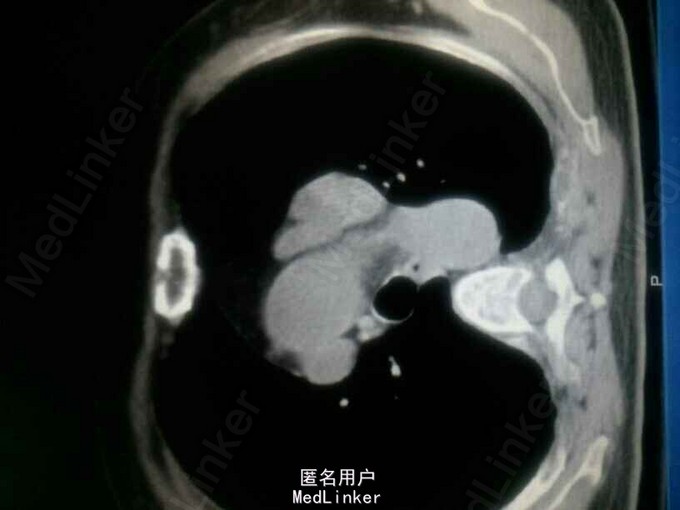

入院后查钾:2.63,钙:3.72,同时尿素氮14.23,肌酐140,碱性磷酸酶672。同时B超提示双肾多发结石。即考虑甲旁亢可能。行PTH:2143。基本明确确诊甲旁亢。但查双侧甲状旁腺B超正常。胸部增强CT提示主动脉弓旁软组织肿块影,双侧多发肋骨骨质破坏。甲状旁腺显像:左胸局部放射性异常摄取。 诊断:异位甲状旁腺肿瘤,甲旁亢,高钙血症,肾结石,病理性骨折。 予降钙等治疗后行剖胸纵膈肿瘤切除术